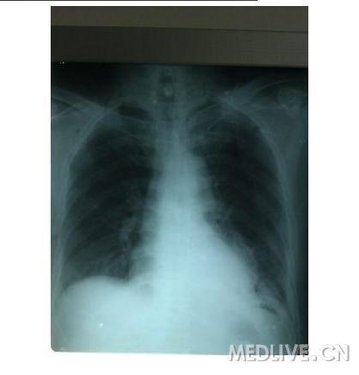

患者男性 60岁 主因进食梗咽感3个月于11-9-29入院,胃镜距门齿34厘米病变 长约1.5厘米 入院后积极术前准备,于10-3日在全麻下行食管癌切除术,术中见癌肿情况尚好与周围无明显浸润,术程顺利。

术后第1天 闭式引流约300ML 为淡血性 第2天 200ml 第三天 100ml 第4天50ml 第五天30ml 拍床头片如下: